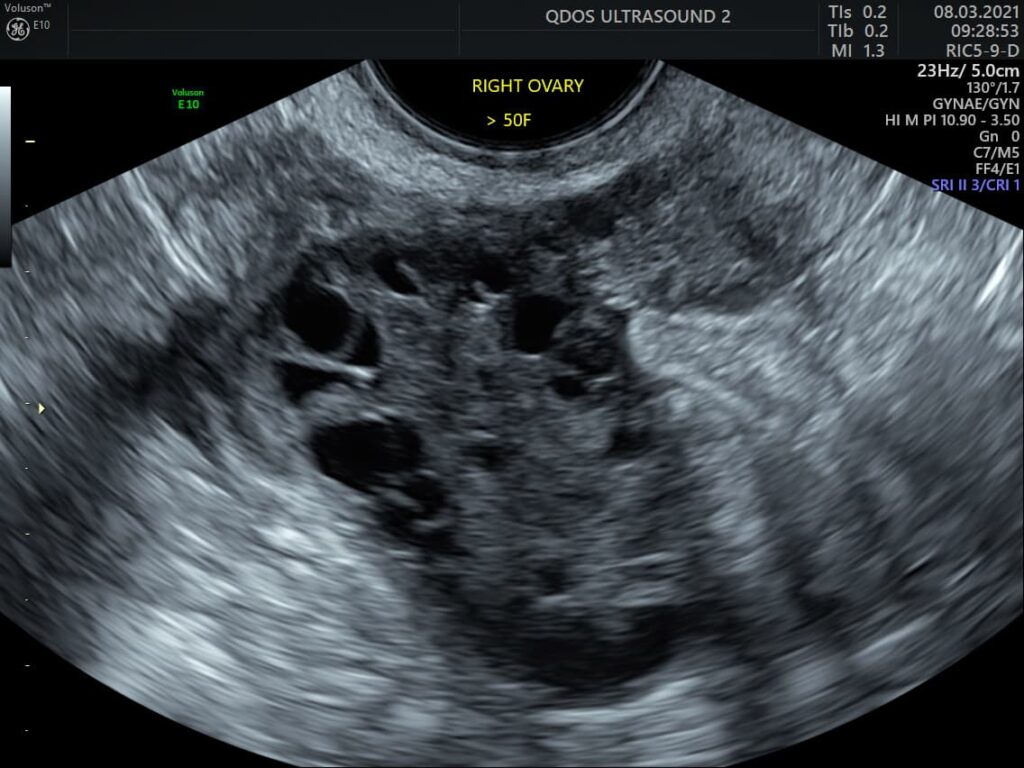

A lack of periods is a common reason your doctor might refer you for a gynaecological ultrasound. This scan can provide valuable insight into various potential causes, such as unusual uterine anatomy or blockages, changes in the uterus lining, and high or low egg count, which may be linked to other medical conditions. Our specialists are skilled in diagnosing conditions like polycystic ovary syndrome (PCOS) and other complex cases requiring expert interpretation.

Ultrasound provides critical information about the ovaries and uterus lining (endometrium) during the menstrual cycle. When periods stop, the scan can help identify causes by assessing ovarian activity and endometrial changes.

Our specialists are skilled in diagnosing conditions like polycystic ovary syndrome (PCOS) and other complex cases requiring expert interpretation.